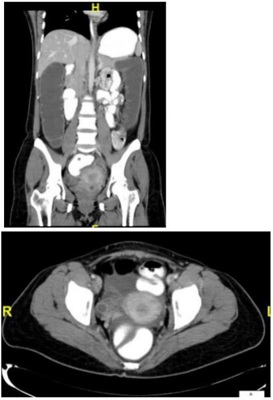

Paciente feminina de 62 anos queixando-se de dor abdominal difusa há 4 dias, em cólicas, associada a distensão abdominal e vômitos fétidos e escuros. Relata que há 4 meses vem apresentando alguns episódios esporádicos de sangramento nas fezes, bem como redução da frequência evacuatória. Nega febre. Nega trauma. Nega cirurgias prévias. Ao exame físico: regular estado geral, descorada, desidratada, anictérica, afebril. Semiologia cardíaca e pulmonar normais. Abdome distendido, com ruídos, doloroso a palpação difusa, sem sinais de irritação peritoneal. Toque retal nota-se lesão ulcerada circunferencial distando 5 centímetros da borda anal. Foras realizadas as radiografias e a tomografia de abdome e pelve abaixo. A conduta mais adequada para este caso é: